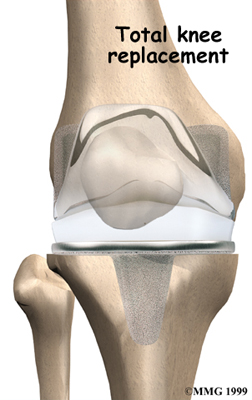

Artificial Knee Replacement

An artificial knee replacement is the ultimate solution for advanced knee OA.

Surgeons prefer not to put a new knee joint in patients younger than 60. This is because younger patients are generally more active and might put too much stress on the joint, causing it to loosen or even crack. A revision surgery to replace a damaged prosthesis is harder to do, has more possible complications, and is usually less successful than a first-time joint replacement surgery.

Related Document: FYZICAL South Sarasota's Guide to Artificial Joint Replacement of the Knee